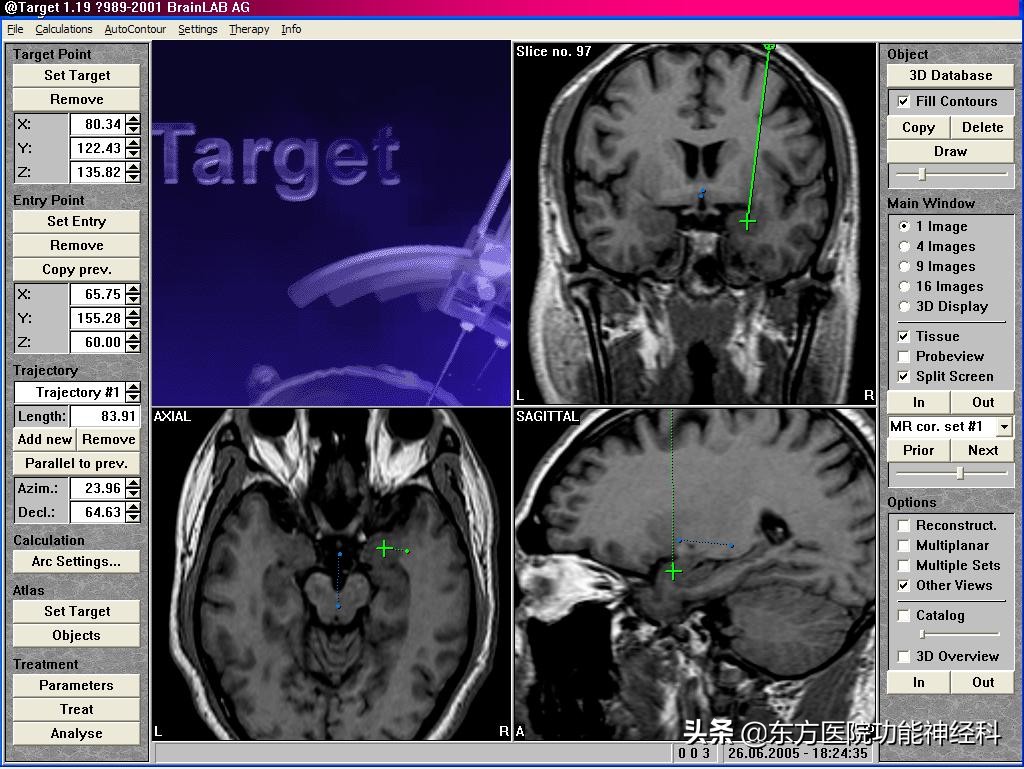

立体定向神经调控术手术计划系统

我院采用的是第五代脑立体定向下微创神经调控术。安全性上,我们配备了美国尼高力数字化长程脑电动态视频检测系统VEEG,该系统具有高采样率、高稳定和病灶精准定位等特点,再结合手术计划系统将DTI、MRI、CT等影像学图像进行融合,精确定位癫痫传导通路的必经之地——脑深部核团。调控异常的神经核团,阻止癫痫全脑放电弥散、即可达到控制癫痫发作、帮助患者回到正常的社会生活的目的。需要特别说明的是,在该手术计划系统中引进的弥散张量成像(DTI)技术可以精确显示脑功能神经传导束,在进行神经调控时有效避开这些神经传导束部位以保证术后患者完整的社会功能。